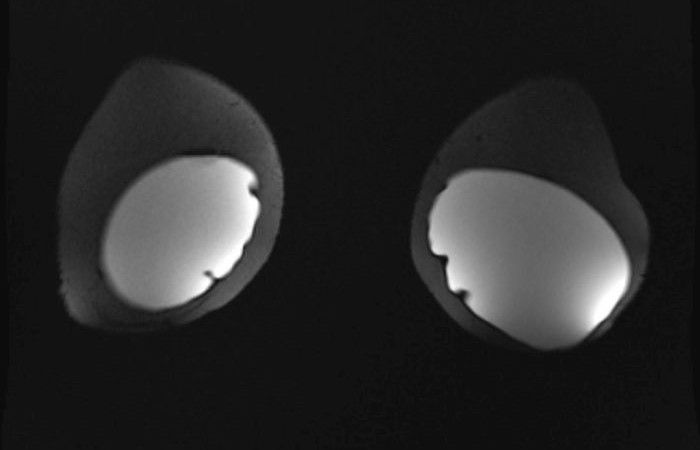

Die Patientinnen liegen während der Untersuchung auf dem Bauch. Die Brust wird in einer speziellen Brustspule platziert.

Während der Untersuchung muss Kontrastmittel in eine Armvene gespritzt werden, um die Durchblutungseigenschaften von verschiedenen Veränderungen analysieren zu können. Deswegen benötigen wir im Vorfeld den Nierenwert, den sogenannten Kreatinin-Wert.

Die Befundung einer Mamma-MRT erfolgt mit Hilfe von Befundkategorien analog nach dem sogenannten BI-RADS-System (Breast Imaging Reporting and Data System). Dieses System wurde von der American College of Radiology entwickelt und dient dazu, Mammographie-, Sonographie- und MRT-Befunde zu standardisieren.

Bei der Befundung einer Mamma-MRT werden verschiedene Aspekte berücksichtigt, darunter die Morphologie des Tumors (also seine Größe, Form und Kontur), die Signalintensität in der MRT, die Kontrastmittelaufnahme und die Lokalisation des Tumors. Auf Basis dieser Faktoren wird der Befund dann in eine von sieben Kategorien eingeteilt, die von Befundkategorie 0 (unvollständige Untersuchung) bis Befundkategorie 6 (histologisch nachgewiesenes Mammakarzinom) reichen.